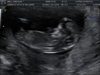

Na wizycie dzis bylam razem z mezem i synkiem, na 80% bedzie dziewczynka

maly siedzial troche zdezorientowany ale podobal mu sie dzidzius, lekarz pokazywal mu usg, nakladali mi razem zel na brzuch, pokazywac gdzie co ma dzidzius